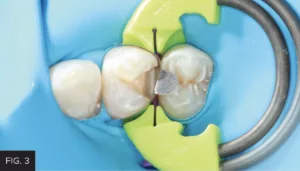

This clinical case highlights a common scenario. (FIG. 1) A Class II carious lesion was detected on the distal of #5. (FIG. 2) The patient was anesthetized via infiltration. Before preparation, a latex free rubber dam (True™ Dental Dam, Clinician’s Choice®) was placed to provide the first line of isolation.